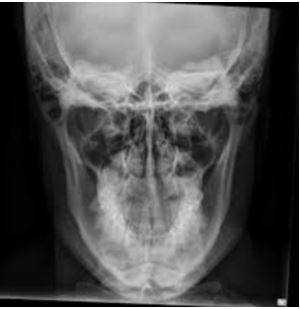

- Рентгенография челюсти. Рентгенологическое исследование - базовый метод диагностики пациентов с подозрением на остеонекроз челюсти. Визуальные изменения костной ткани включают реактивный периостальный остеогенез, уплотнение твердой пластинки альвеолы, утолщение дна верхнечелюстного синуса. С помощью рентгенографии также определяются очаги костной деструкции.

Рентген, а лучше КТ (компьютерная томография) помогает определить площадь патологического процесса, степень поражения, наличие переломов, секвестров (отмерших фрагментов кости, свободно лежащих между здоровых тканей).

Полученный результат рентген-снимка оценивают исключительно в одной плоскости, что не дает развернутой картины происходящего. Костные образования могут заходить друг за друга, и рентгенолог не всегда может четко отличить накладывающиеся изображения.

КТ, напротив, дает объемную трехмерную модель органа, верхнюю и нижнюю челюсть можно оценить сразу в нескольких проекциях и посмотреть даже внутреннюю структуру костей.